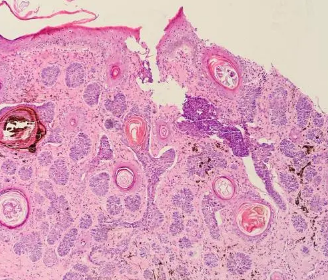

随着精准医疗的发展,靶向药物治疗和免疫治疗在基底细胞癌中的应用也有了新的进展。皮肤科BCC是一种皮肤癌,全称为皮肤基底细胞癌,是最常见的皮肤恶性肿瘤,是比较容易治愈的一种疾病。基底细胞癌BCC通常生长在皮肤表层下面,通常出现在面部、头皮、手臂、胸部、腿部等部位,基底细胞癌症症状的表现包括皮肤上出现红色、白色或粉色的斑块,有时会出现溃疡或结痂。一般情况下,基底细胞癌BCC生长缓慢,较少转移,且通常是无痛性的,但亦可局部浸润性生长,可能会扩散到周围组织或转移到其他器官,破坏组织和器官,引起器官功能障碍,甚至危及患者生命。近年来,分子诊断、 Mohs显微描记手术、光动力疗法等技术的发展,推进了BCC的诊断和治疗。对于治疗及时且充分的患者一般能存活5-30年,但晚期基底细胞癌患者的一般生存时间仅为半年左右。基底细胞癌的发病原因1、紫外线暴露

皮肤是人体健康的第一道防线,随着年龄的增长,皮肤作为人体最大的器官,也在发生一系列的退行性变化,如乏脂性湿疹、老年斑、老年性血管瘤、老年性白斑、老年性紫癜等。有些老年肿瘤性皮肤病,不但影响皮肤的正常功能,还会带来不同程度的病痛,甚至影响生命。尤其是在紫外线较强的地区,老年人颜面部皮肤出现黑色肿物,有可能是基底细胞癌的癌症症状,要小心皮肤癌症! 最常见的皮肤癌类型之一是基底细胞癌(BCC)。虽然病程进展缓慢,但是发生侵袭性生长后就有一定转移风险,危及生命,所以在最早期及时就医,早诊断,早治疗。 BCC为来自基底细胞的恶性肿瘤,它与日光照晒有密切关系,所以BCC多见于老年人头、面、颈及手背等处,尤其是面部较突出的部位。开始是一个皮肤色到暗褐色浸润的小结节,较典型者为蜡样、半透明状结节,有高起卷曲的边缘。BCC发展缓慢,但是如不予及时治疗,中央常破溃,结黑色坏死性痂,缓慢向深部组织侵犯,特别是在面部,可破坏鼻、耳、眼眶和上颌窦等处的软骨或骨骼,引起颅内侵犯和肺转移。基底细胞癌鉴别诊断